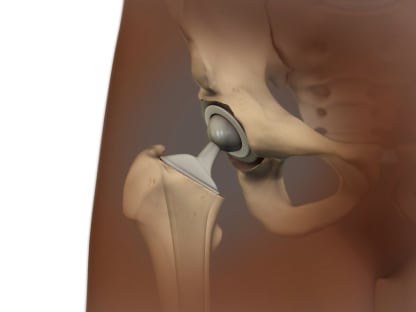

- Joint replacement.

This is done when other treatments haven't worked and damage to the joint can be seen on X-rays. It involves surgery to replace the ends of bones in a damaged joint. The surgery creates new joint surfaces. The joints that are replaced most often are the hip, knee, and shoulder. But other joints such as the elbow and the ankle can also be replaced.

- Hip resurfacing surgery.

This is most often done in younger, more active people who have pain and disability caused by a badly damaged hip.